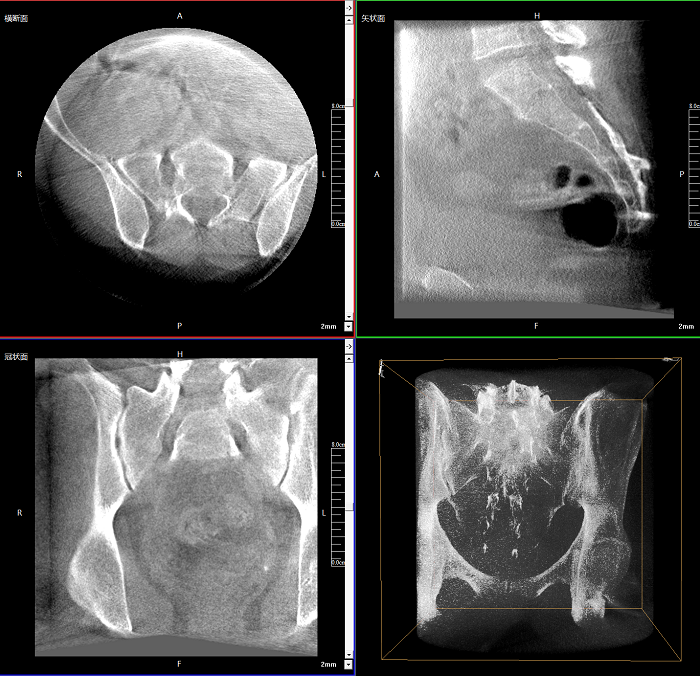

術中CT檢查 減少翻修概率

通過術中三維影像的檢查,可以立即發(fā)現(xiàn)植入物的錯位,減少不必要的第二次手術,減少并發(fā)癥概率以及感染風險。